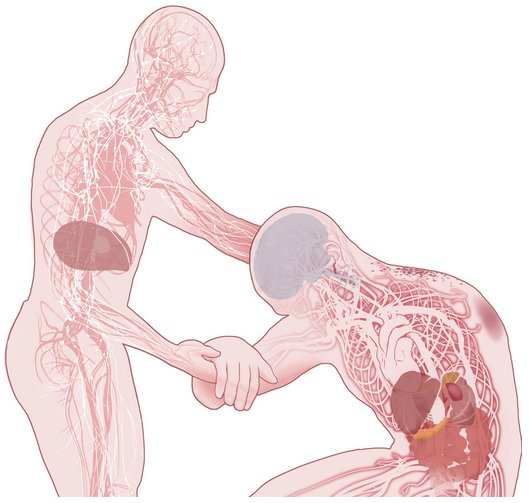

ویروس ابولا، قبل از اینکه از نابودی آبشاری سیستم ایمنی بدن، عروق خونی و اندام های حیاتی را آغاز کند، می تواند برای بیش از یک هفته در بدن پنهان بماند.

شروع

ذرات ویروس ابولا خون فرد آلوده و سایر مایعات بدن وی را اشغال می کند، این مایعات آلوده می توانند از طریق چشم ها، غشاهای مخاطی، خراشیدگی های روی پوست و یا از یک سوزن تزریق زیر جلدی وارد بدن شخص دیگری شود. اجساد افرادی که از این بیماری فوت کرده اند، بسیار خطرناک هستند. در روستاهای کوچک در غرب آفریقا، ارائه مراقبت شخصی نزدیک به بیمار یا اعضای خانواده فرد فوت شده به راحتی می تواند این بیماری را گسترش دهد.

مرحله حمله

ویروس به سلول های ایمنی در جریان خون حمله می کند، و عفونت را به کبد، طحال و گره های لنفاوی انتقال می دهد. ابولا از انتشار اینترفرون، یک پروتئین ساخته شده توسط سلول های ایمنی برای مبارزه با ویروس، جلوگیری می کند.

سلول های ایمنی آلوده از طریق جریان خون یا مجراهای لنفی به دیگر بافت ها و اندام ها، به خارج از طحال و گره های لنفاوی، انتقال می یابند.